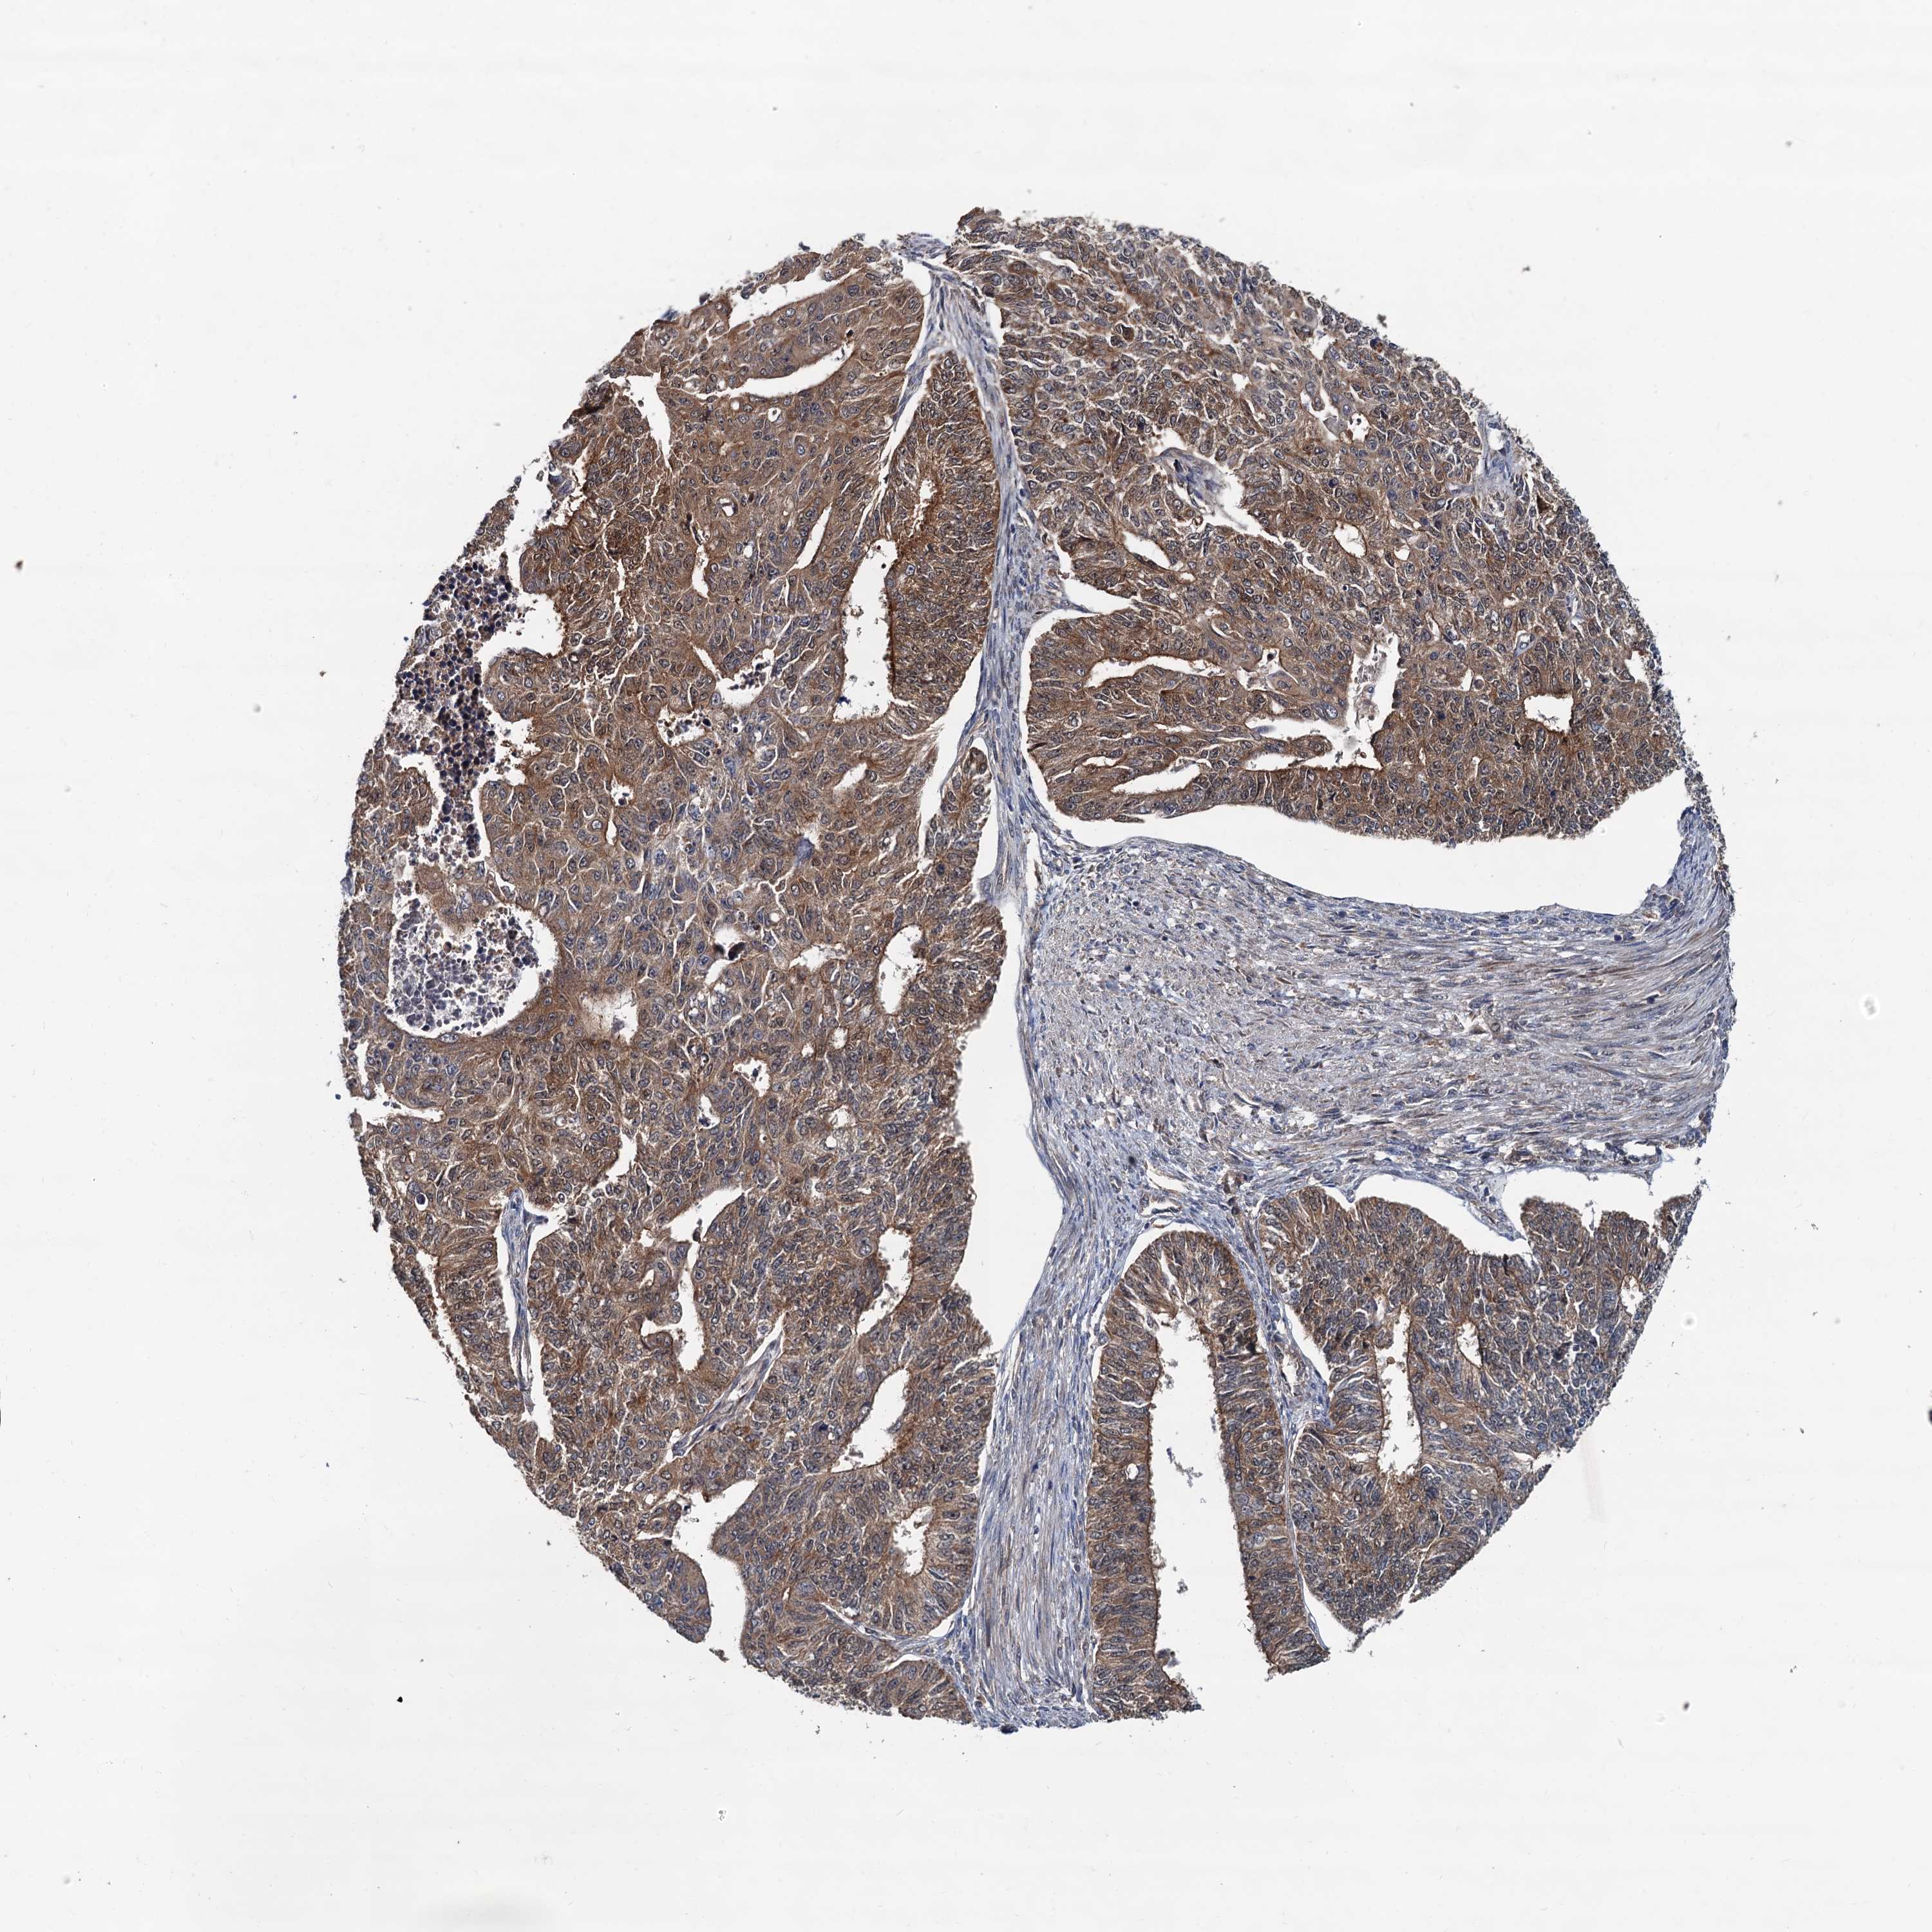

ENDOMETRIAL CANCER - Protein expressioni

A mouse-over function shows sample information and annotation data. Click on an image to view it in a full screen mode. Samples can be filtered based on level of antibody staining by selecting one or several of the following categories: high, medium, low and not detected. The assay and annotation is described here.

Note that samples used for immunohistochemistry by the Human Protein Atlas do not correspond to samples in the TCGA dataset.

Antibody stainingi

Antibody staining in the annotated cell types in the current human tissue is reported as not detected, low, medium, or high, based on conventional immunohistochemistry profiling in selected tissues. This score is based on the combination of the staining intensity and fraction of stained cells.

Each image is clickable and will lead to virtual microscopy that enables deeper exploration of all samples and also displays staining intensity scores, fraction scores and subcellular localization as well as patient and tissue information for each sample.

Antibody HPA039371

Antibody HPA040174

Staining

High

Medium

Low

Not detected

Intensity

Strong

Moderate

Weak

Negative

Quantity

>75%

75%-25%

<25%

None

Location

Nuclear

Cytoplasmic/membranous

Cytoplasmic/membranous,nuclear

Adenocarcinoma, NOS